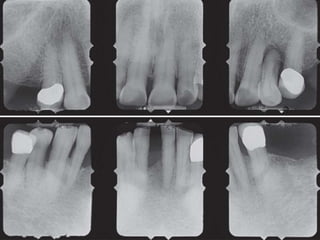

Bone loss

 Type 2 diabetes mellitus is associated with

significantly increased risk of progressive

bone loss. Taylor GW,1998

 There is increasing prevalence of alveolar

bone loss as glycemic control worsened.

 The mean percentage of sites with > 15%

bone loss went from 28% in well

controlled type 1 diabetes mellitus

subjects to 44% in poorly controlled

subjects. Tervonen et al. 2000